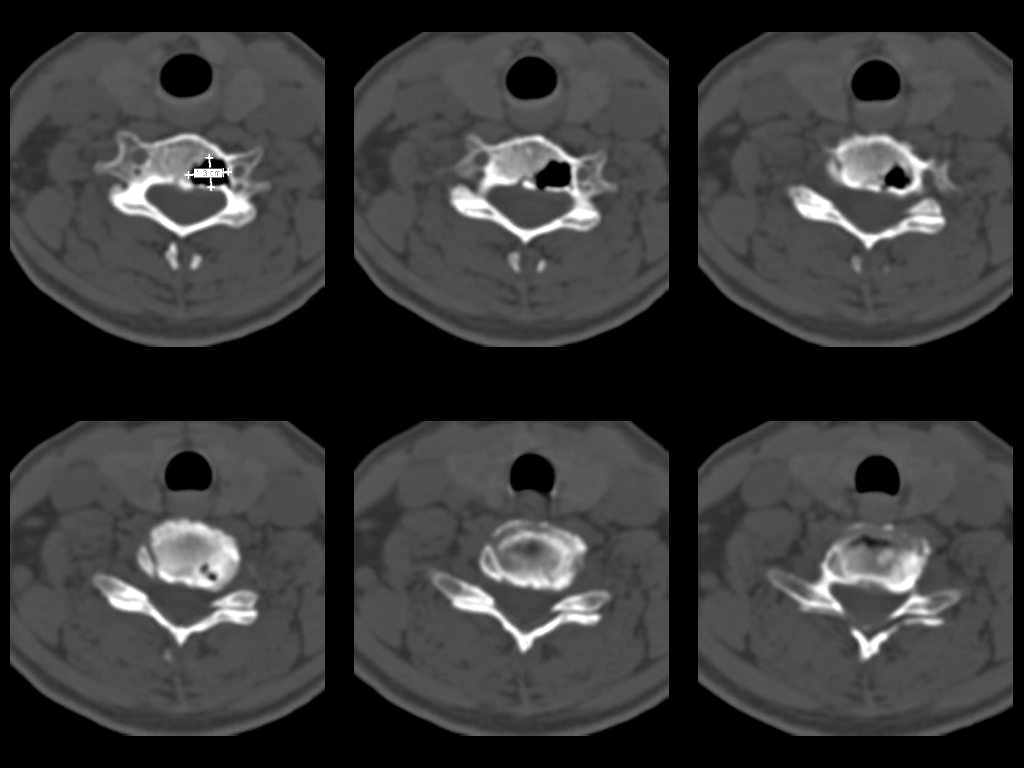

У женщины 49 лет, при рентгенографии шейного отдела в теле С6 выявлен участок деструкции.Часть N1 Больная находилась в неврологическом отделении с диагнозом энцефалопатия. Была проведена КТ тела С6, 26.12.2002 выявлен участок деструкции 0,9х1,2 см, плотность участка составляет -1022 ед.Н. аналогичная плотности воздуха в трахее.Возникает вопрос что это? Метастаз, киста,или какой то вредный анаэроб грызет тело позвонка?Через пол года 03.06.2003 произведено повторное исследование. Отмечается отрицательная динамика. Участок деструкции увеличился в размерах, увеличелась площадь разрушения задней поверхности тела С6.

Первые 2 серии снимков это от 2002г, вторые 2 серии от 2003 г. Относительно размеров, сообщю дополнительно все перермерю на томографе.

Размеры за 2002 год 1,2х0,9х1,2 мм

за 2003 1,3х0,9х1,2 мм. Но контур деструкции стал более неровный и внедрение в дужку С6 увеличелось.